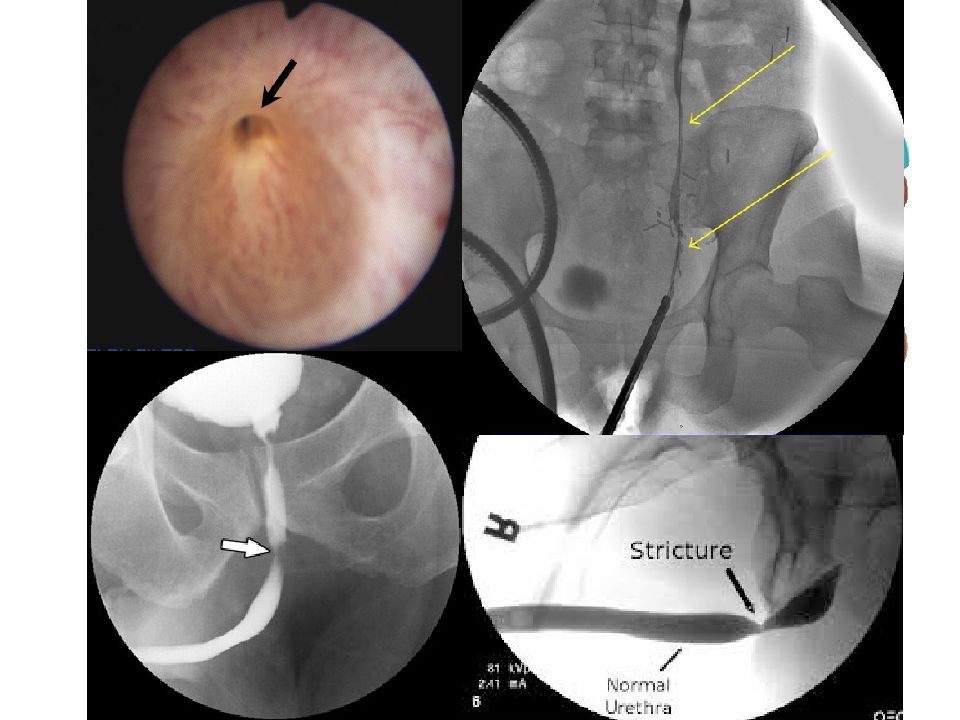

Слайд 44

Стриктура холедоха Стриктура холедоха, желчная гипертензия, миграция клипс, билома Стенозирующий папиллит